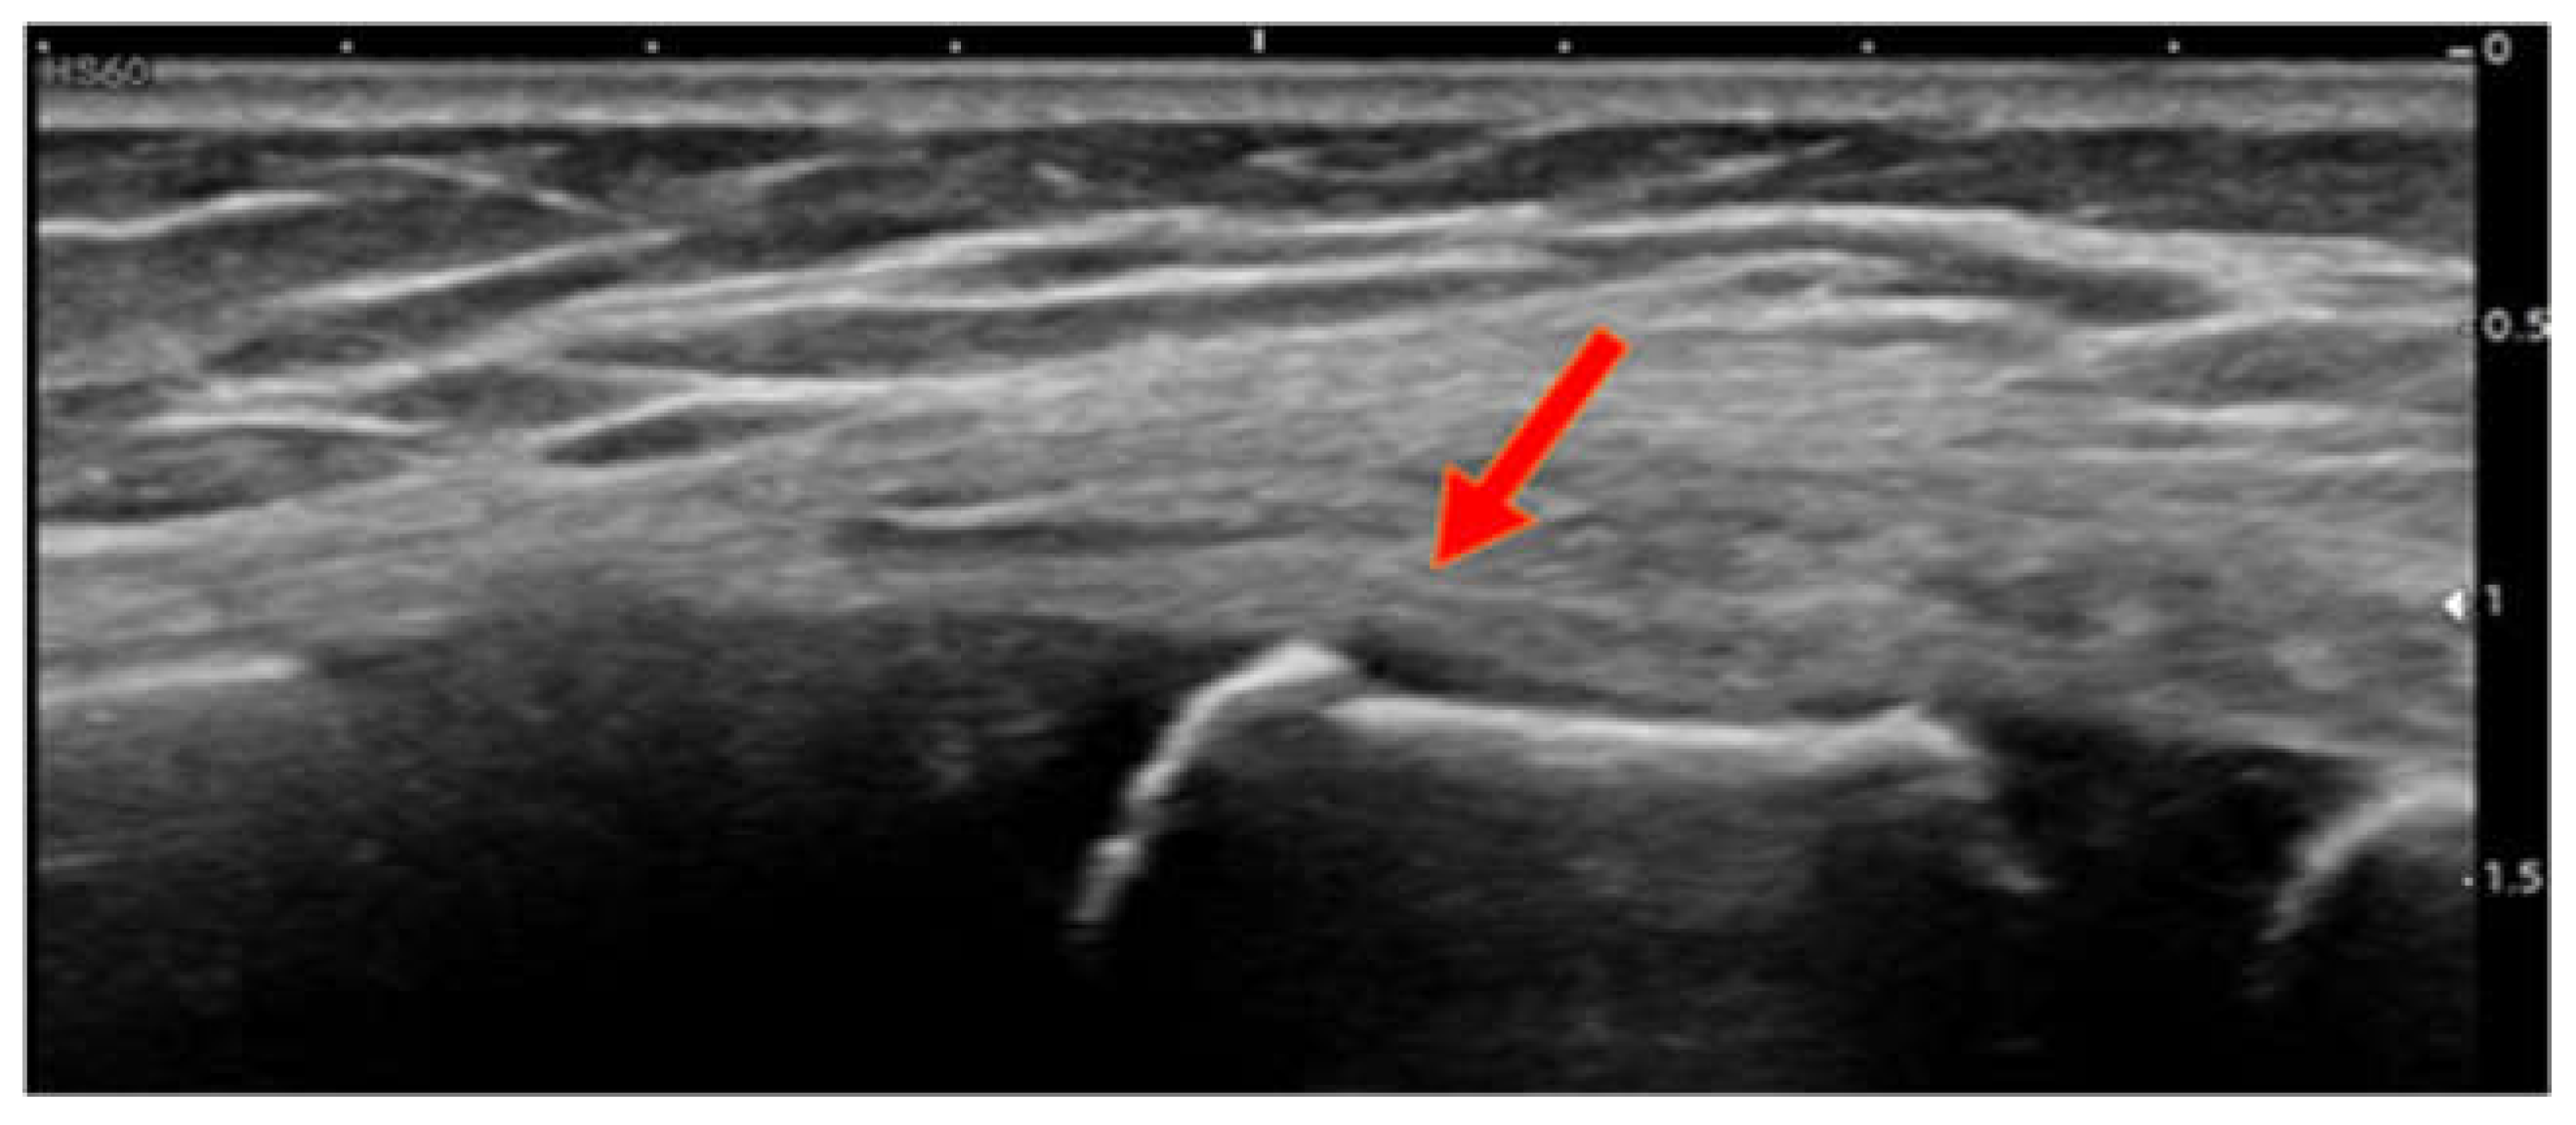

Children Free FullText POCUS Diagnosis of Sternal Fractures in What Happens If Your Sternum Cracks a sternum fracture is a break of the breastbone in the middle of the chest, often caused by trauma or cpr. call your doctor now or seek immediate medical care if: Learn how to recognize the signs, possible complications and treatment options for a fractured or bruised sternum. The main symptom is chest. in this blog, we’ll. What Happens If Your Sternum Cracks.

Children Free FullText POCUS Diagnosis of Sternal Fractures in What Happens If Your Sternum Cracks a sternal fracture is a break in the breastbone, often caused by blunt chest trauma or cpr. a broken sternum is a fracture in the breastbone, usually caused by trauma to the chest. You have new or worse trouble breathing. It can result from muscle spasms, injuries, arthritis, or other conditions. a sternum fracture is a break. What Happens If Your Sternum Cracks.